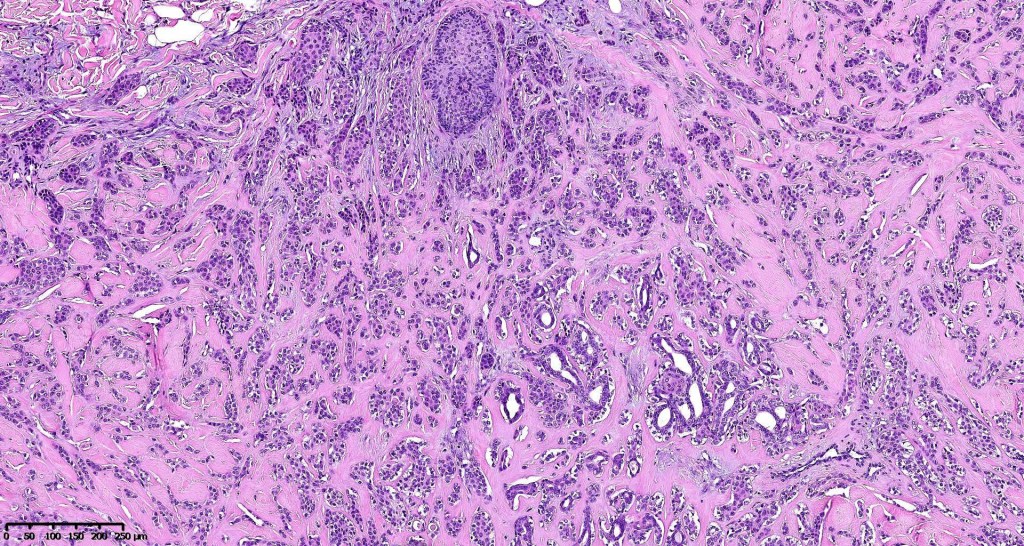

•Well circumscribed unencapsulated, nodular/multinodular silhouette composed of an admixture of epithelial & mesenchymal elements

•Mixed epithelial component including nests & cords of epithelium with abundant, eosinophilic cytoplasm & small vesicular nuclei

•Glandular differentiation sometimes showing apocrine differentiation

•Myoepithelial layer in glandular foci

•Ductal differentiation

•Cribriform/retiform appearance occasionally evident

•Myxoid change